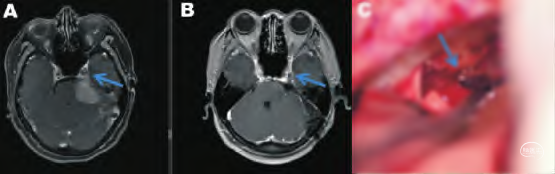

岩斜脑膜瘤(箭头示肿瘤侵袭海绵窦)切除,枕下乙状窦后入路

A.术前;B.术后;C. 以匙形刀头切除岩尖骨质